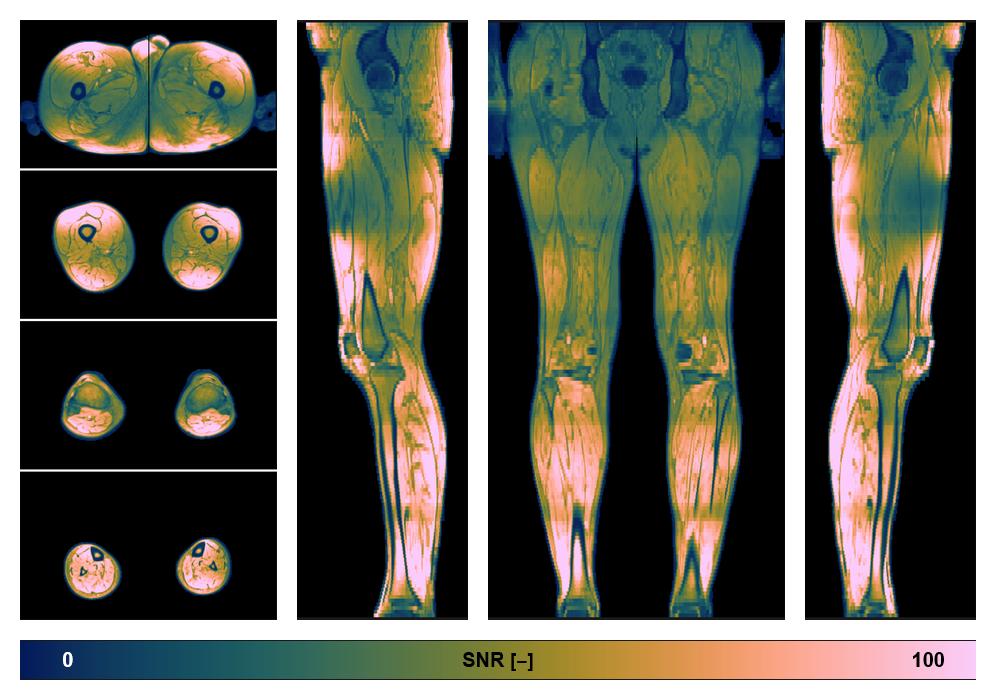

• SNR distribution

The SNR distribution of the dixon data.

• SNR of the unweighted image

SNR distribution of the unweighted diffusion data.